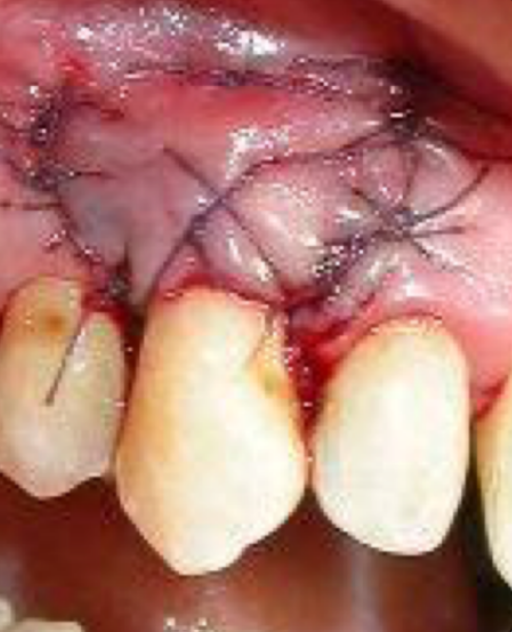

This is the final step where the graft is placed into the recipient site and secured with stitches.